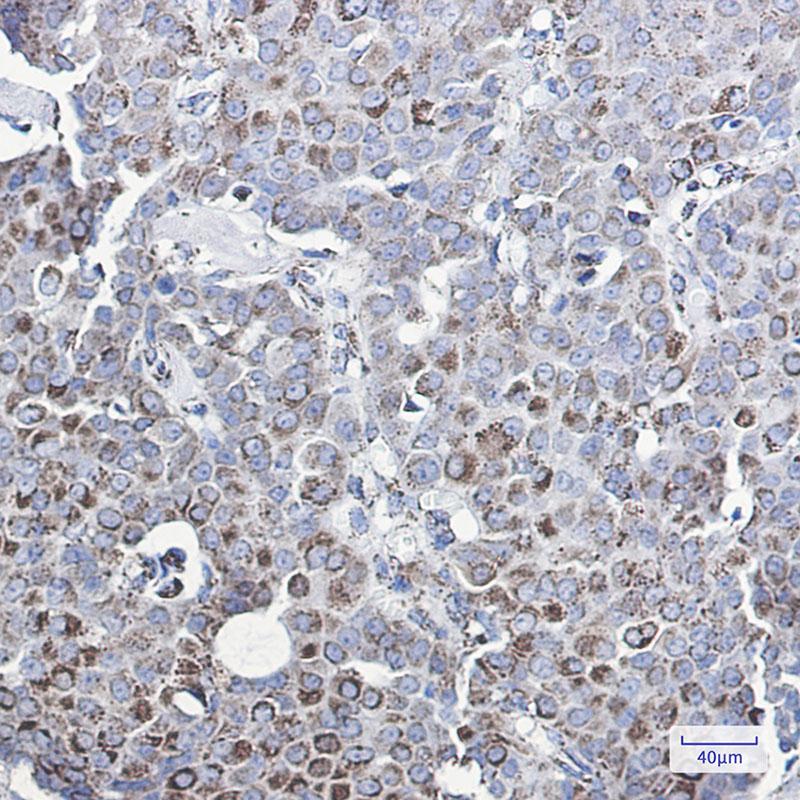

MMP3 Rabbit mAb

| WB, IHC-P |

| Dilution | WB~~1:1000-1:5000 IHC-P~~1:50~200 |